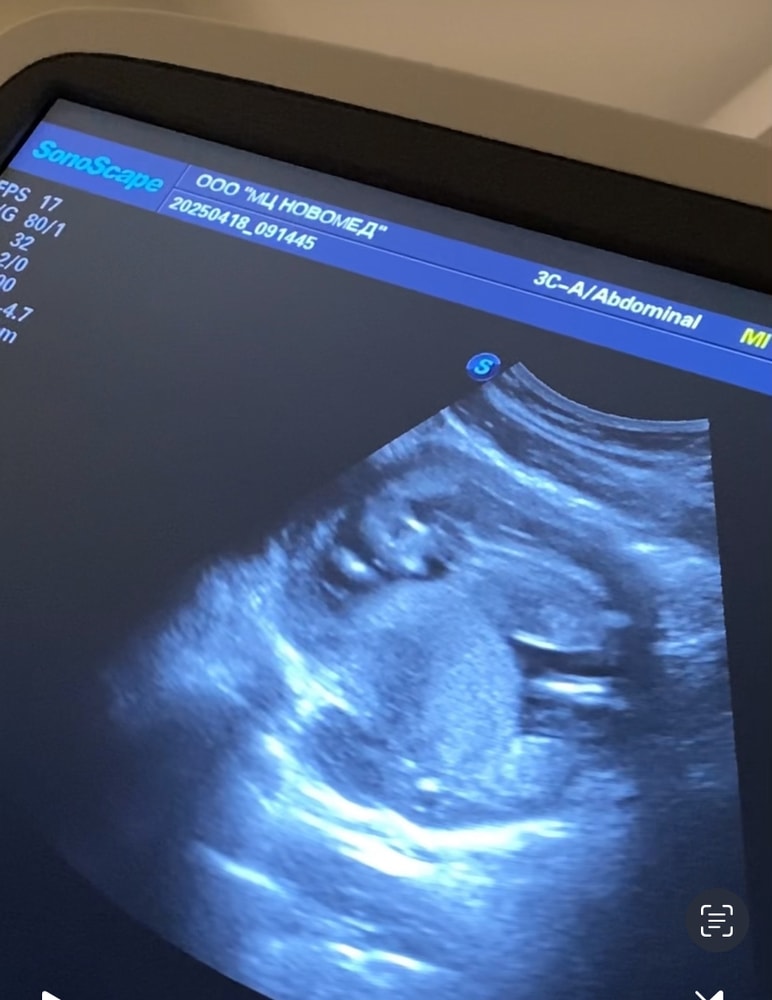

Nika, полет нормальный 😁😁😁👌 Изображение

21.04.2025

Краевое прикрепление пуповины и перекрытие зева, низкое расположение плаценты Результаты первого скрининга